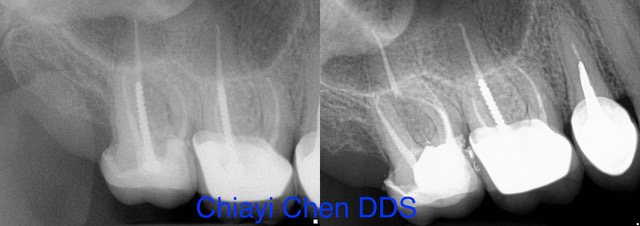

- X-ray findings: Regular dental checkups include X-rays to monitor any changes in your teeth and roots over time. These images can reveal signs such as new infections or persistent infection despite previous treatment.

The endodontist will start by taking X-rays to assess the condition of the tooth and determine if re-treatment is necessary. They will also administer local anesthesia to ensure your comfort throughout the procedure. Next, they will carefully remove any previous filling material and clean out the canals thoroughly. This may involve using special tools to remove stubborn bacteria or debris. Once the canals are cleaned, they will be reshaped and disinfected before being filled with a new rubber-like material called gutta-percha. The endodontist may also place a temporary filling on top for added protection.